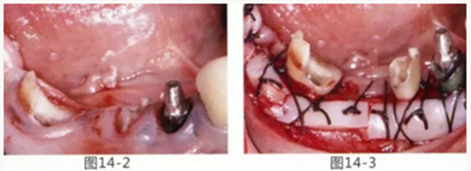

圖14-1 修復體周圍角化牙齦較少,很難進行清潔的狀態(tài),并有緣下齲壞的發(fā)生。

圖14-2,3 徹底去除齲壞后,試圖通過游離齦移植獲取生物學寬度和附著齦。

圖14-4~6修復體周圍角化牙齦較少,很難進行清潔的狀態(tài),并有緣下齲壞的發(fā)生。

圖14-7 配戴最終修復體完成5年后的狀態(tài)。保持良好。